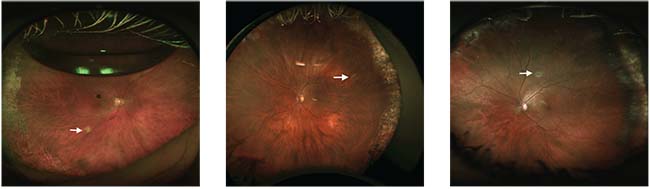

| Figure 2. A poorly performed drainage retinotomy (A) is too posterior and too large. Despite single-operation success, the patient is unhappy because of a visual scotoma. This retinotomy (B) is not as symptomatic, and although the scotoma is apparent to the patient, it is not as bothersome as that in Figure 2A because it is farther from optic nerve and is in the superior field of view, which is often less noticeable. However, it is still unnecessarily large. |

I perform external drainage on almost all cases of retinal detachment repair without vitrectomy (41/43). I use a short, 25-gauge needle for drainage, for which I sometimes use indirect ophthalmoscopic visualization (Figure 2). Rarely I will perform a posterior sclerotomy and suture the sclerotomy, usually on chronic detachments when the subretinal fluid is very thick.

| Figure 3. Retinotomies should be like these three, as highlighted with arrows: small and visually insignificant. |

I try to make my posterior retinotomies not too posterior—usually several disc diameters from the optic nerve and arcades—to reduce the risk of visual scotomas; and I try to keep the size under 1 disc diameter (Figure 3).